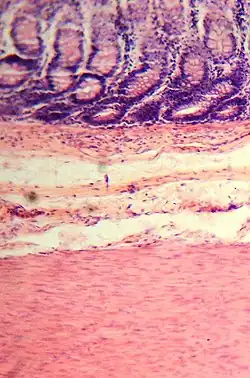

Feinbau

Der Dickdarm zeigt den typischen Wandaufbau des Magen-Darm-Traktes mit vier Schichten. Die innerste Schicht ist eine Schleimhaut (Tunica mucosa, kurz Mukosa), die ihrerseits aus drei Schichten aufgebaut ist: die Oberfläche ist mit Epithel (Lamina epithelialis) bedeckt, das durch lockeres Bindegewebe (Lamina propria mucosae) von einer Schicht aus glatten Muskelzellen (Lamina muscularis mucosae) getrennt ist. Die Schleimhaut liegt einer lockeren Bindegewebsschicht (Tunica submucosa, kurz Submukosa) auf. Diese führt die Blut- und Lymphgefäße für die Mukosa und beinhaltet ein Nervengeflecht, den Plexus submucosus. Sie dient zudem als Verschiebeschicht zur dritten Wandschicht, der Tunica muscularis, die dem Organ mit einer inneren Ringmuskelschicht (Stratum circulare) und einer äußeren Längsmuskelschicht (Stratum longitudinale) peristaltische Bewegungen ermöglicht. Zwischen den Muskelschichten liegt ein weiteres Nervengeflecht, der Plexus myentericus, der ebenso wie der Plexus submucosus zum enterischen Nervensystem gehört. Die vierte Schicht ist je nach Abschnitt des Dickdarms entweder lockeres Bindegewebe (Adventitia) oder das Bauchfell.[21]

Ein wichtiger feinbaulicher Unterschied zum Dünndarm besteht in dem Fehlen von Darmzotten, die Dickdarmschleimhaut hat nur tiefe Krypten, die von zylinderförmigen Zellen (hochprismatisches Epithel) ausgekleidet sind. Viele dieser Zellen produzieren Gleitschleim, andere nehmen Wasser auf und dicken so den Stuhl ein. Auch die Dickdarmwand ist wie die Wand des Dünndarms in Falten geworfen. Diese entstehen aber durch örtliche Einziehungen der inneren Ringmuskelschicht, die im Querschnitt halbmondförmig erscheinen (daher der lateinische Name Plicae semilunares). Zwischen den Einziehungen bildet die Darmwand Aussackungen, die als Haustren (deutsch: Poschen) bezeichnet werden. Bei einigen Säugetieren, auch beim Menschen, ist die äußere Längsmuskelschicht zu drei kräftigen Strängen (Tänien) verdickt. An diesen Tänien hängen außen Ansammlungen von Fettgewebe (Appendices epiploicae).[22] Von diesem Muster weicht die Appendix vermiformis ab. Sie hat keine Tänien, sondern wie die anderen Abschnitte des Verdauungstraktes eine durchgehende Längsmuskelschicht. In der Lamina propria der Schleimhaut sind große Lymphfollikel zu finden.[23] Das Rektum hat statt der Tänien eine durchgehende Längsmuskelschicht, keine Haustren und keine Fettanhängsel.[24] Am Analkanal geht das Epithel des Rektums in mehrschichtig unverhorntes Plattenepithel über.[25]